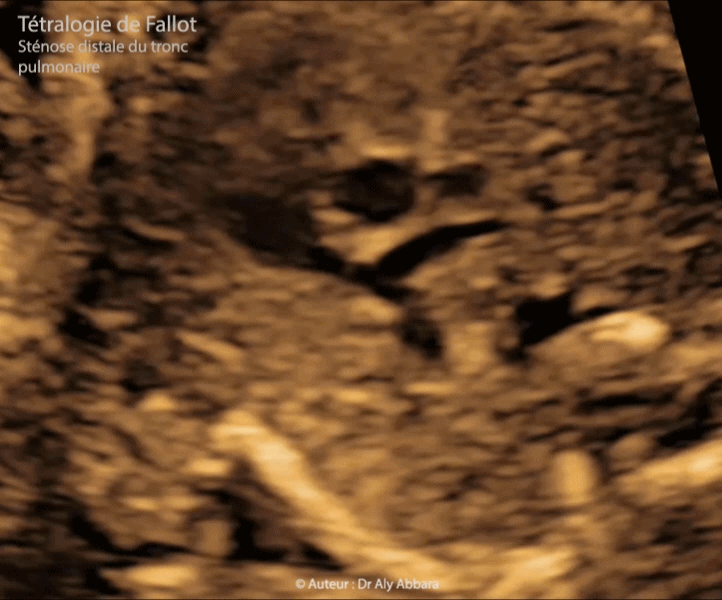

• I - Coupe de la voie pulmonaire mettant en évidence le tronc pulmonaire et ses deux branches (artère pulmonaire droite et gauche) :

• Une sténose de la portion distale (supravalvulaire) du tronc pulmonaire avec la disparité de calibre entre aorte et tronc pulmonaire (anneau pulmonaire hypoplasique mesurant 3 mm pour un anneau aortique mesurant 6 mm).

Présence de deux artères pulmonaires : de 2,7 mm de calibre à droite et de 2,3 mm à gauche.